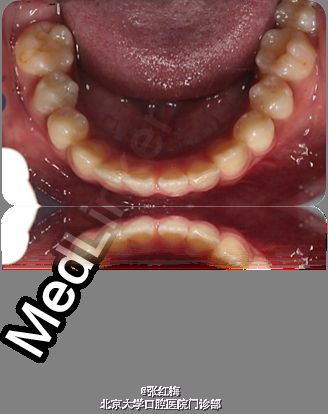

9岁儿童,女 主诉:右下后牙肿痛2天,伴舌侧牙龈肿痛,求治。 现病史:患儿3周前右下后牙畸形中央尖折断,行畸形中央尖备洞充填治疗,2周后出现右下后牙自发痛夜间痛,时间短暂,未就诊,3周后右下后牙肿痛,舌侧牙龈肿痛就诊求治。